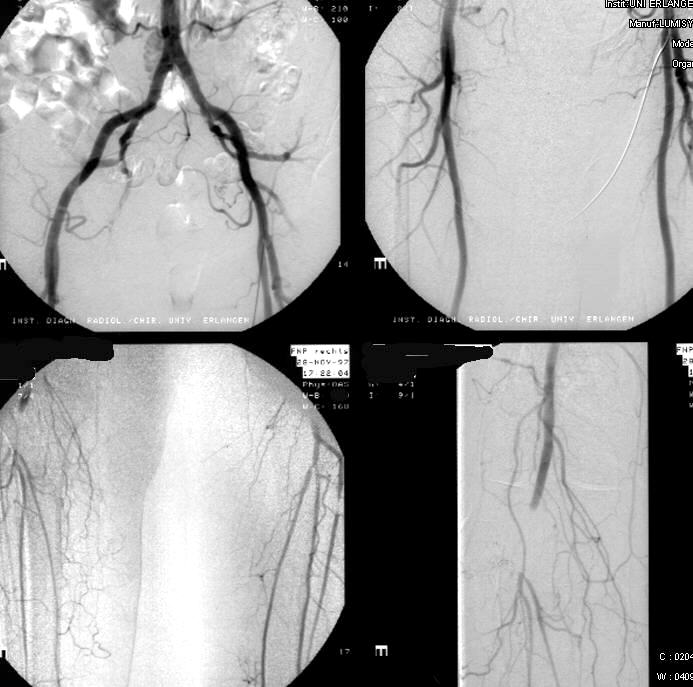

Collection IDR University of Erlangen-Nuermberg, Germany< >Subraktionsangiographie der Beckenbeinarterien mit transfemoralem Zugang li.- Nachweis einer Embolie der distalen A. poplitea re. Nebenbefund: Stenose der A. tibialis li. und der A. fibularis li. im Abgangsbereich